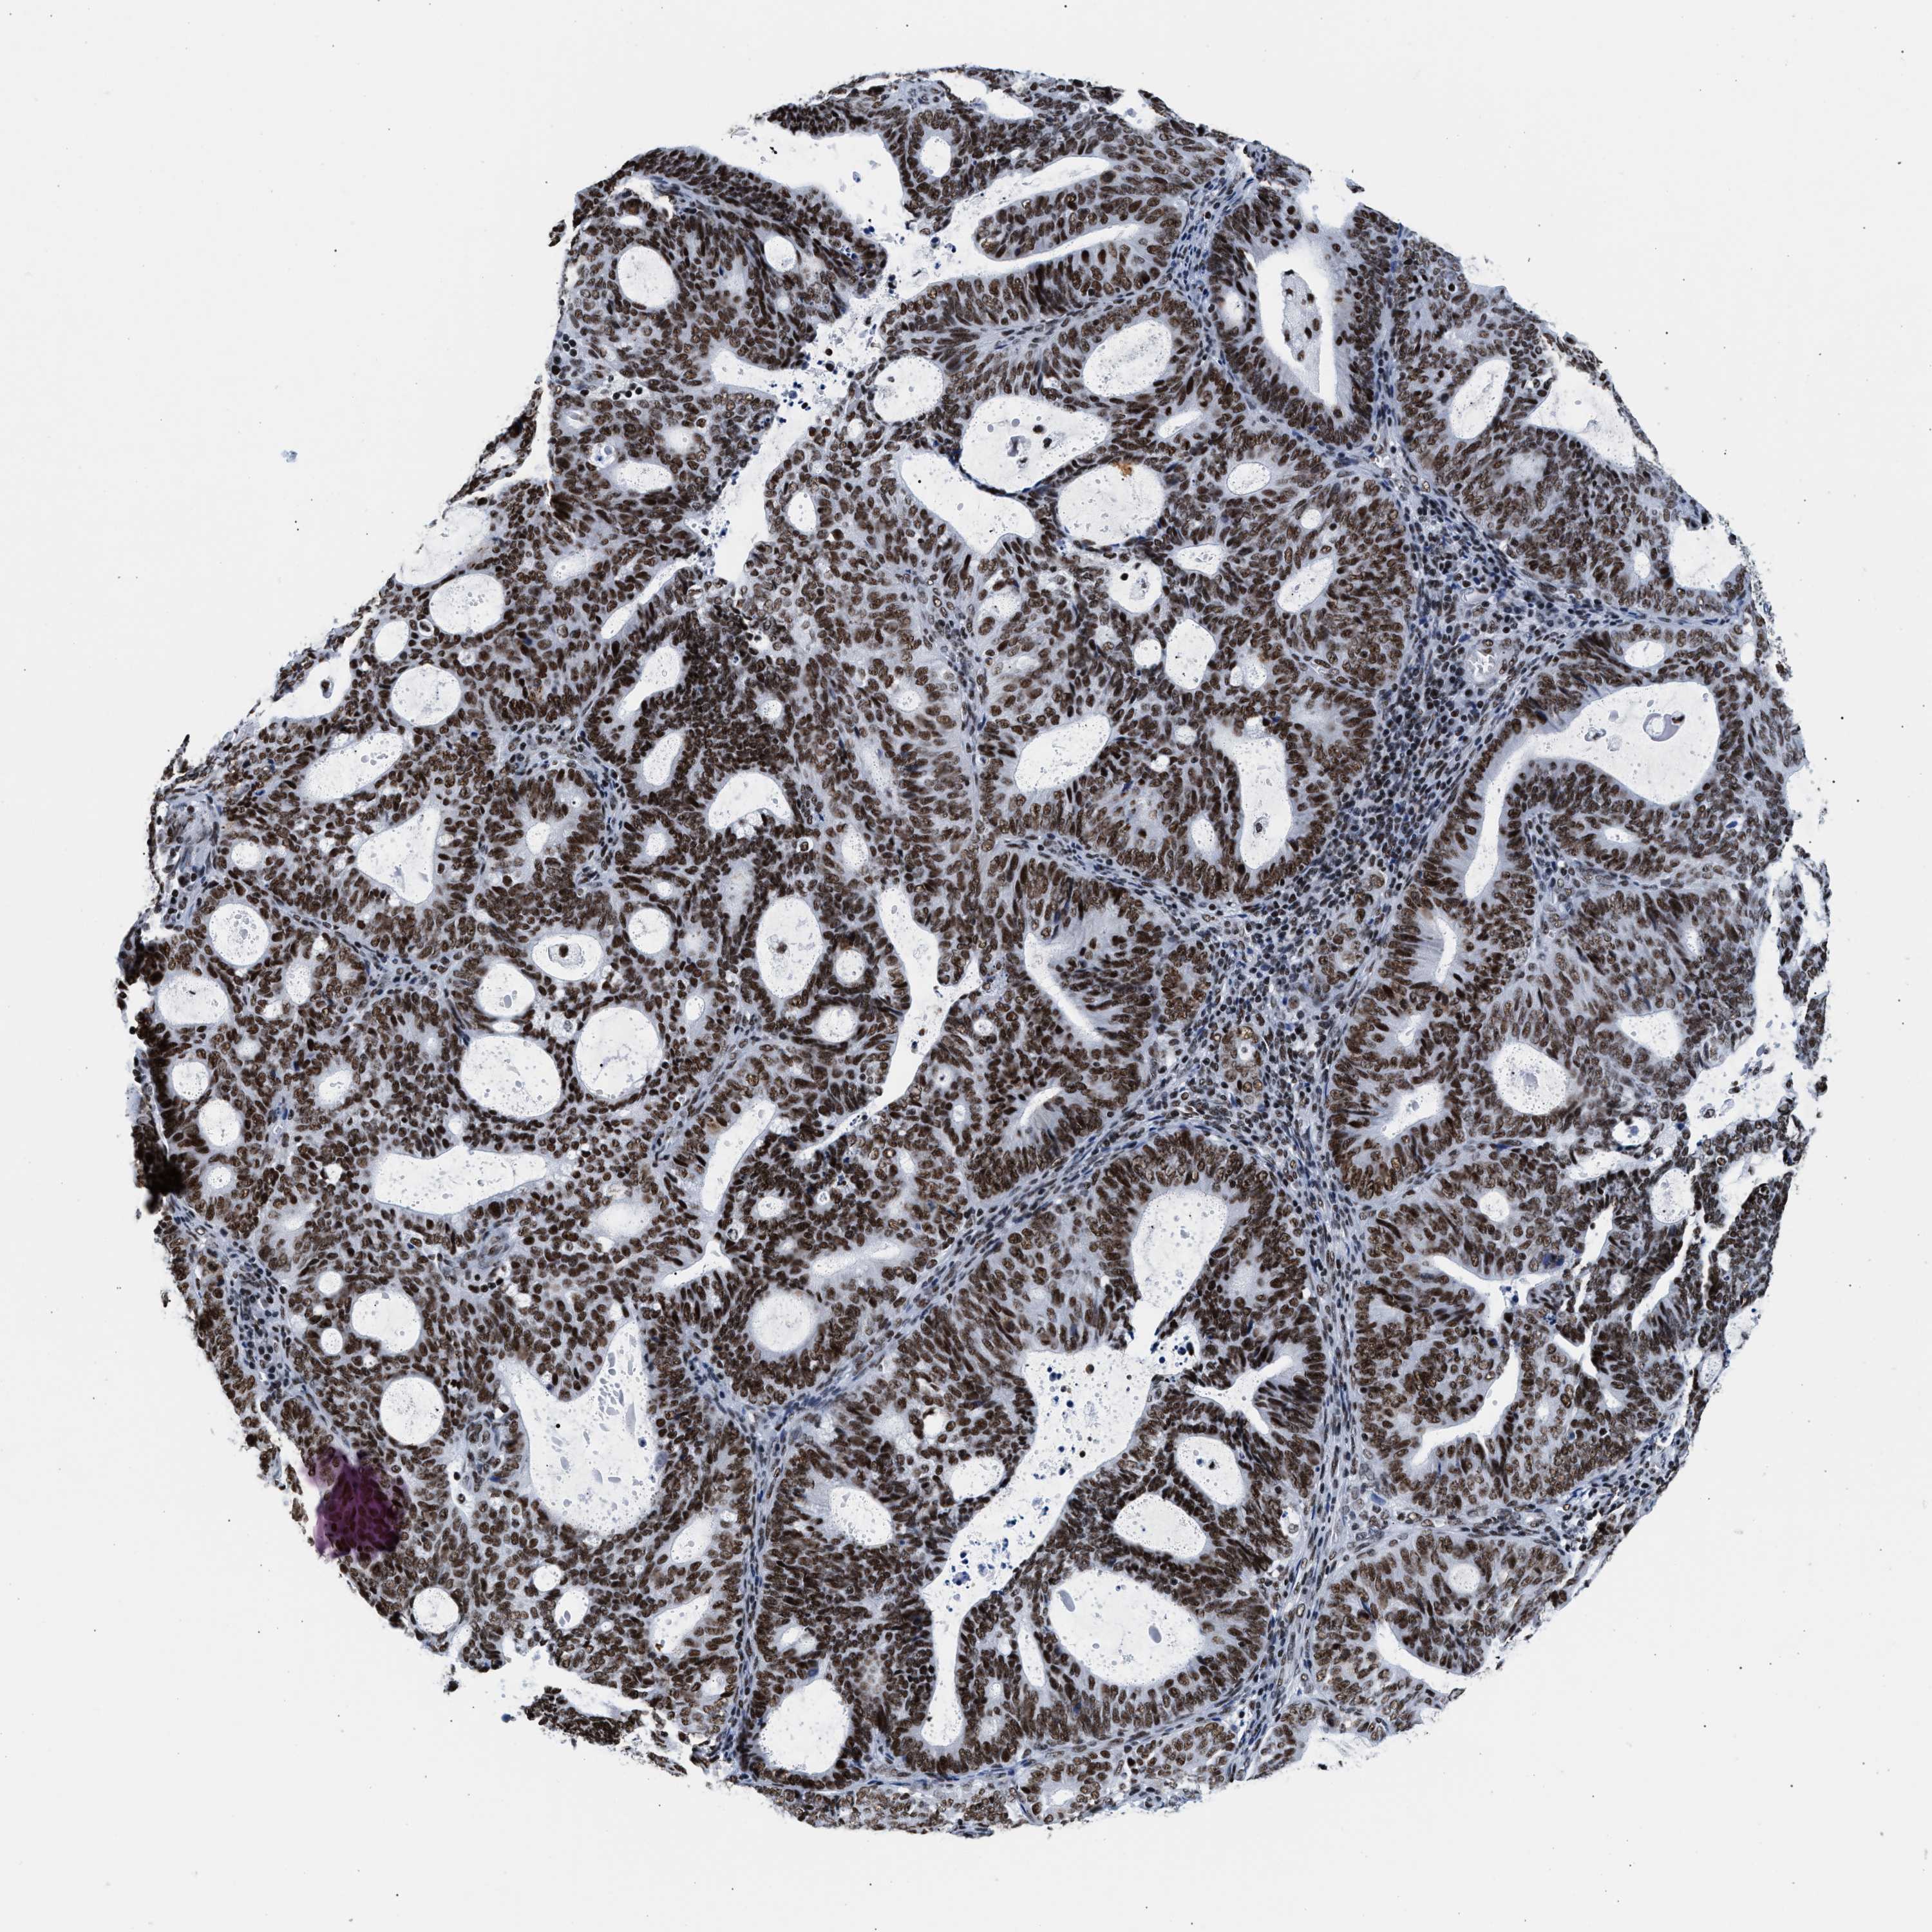

ENDOMETRIAL CANCER - Protein expressioni

A mouse-over function shows sample information and annotation data. Click on an image to view it in a full screen mode. Samples can be filtered based on level of antibody staining by selecting one or several of the following categories: high, medium, low and not detected. The assay and annotation is described here.

Note that samples used for immunohistochemistry by the Human Protein Atlas do not correspond to samples in the TCGA dataset.

Antibody stainingi

Antibody staining in the annotated cell types in the current human tissue is reported as not detected, low, medium, or high, based on conventional immunohistochemistry profiling in selected tissues. This score is based on the combination of the staining intensity and fraction of stained cells.

Each image is clickable and will lead to virtual microscopy that enables deeper exploration of all samples and also displays staining intensity scores, fraction scores and subcellular localization as well as patient and tissue information for each sample.

Antibody HPA020044

Antibody CAB022065

Staining

High

Medium

Low

Not detected

Intensity

Strong

Moderate

Weak

Negative

Quantity

>75%

75%-25%

<25%

None

Location

Nuclear

Cytoplasmic/membranous

Cytoplasmic/membranous,nuclear

Adenocarcinoma, NOS

Adenoma, NOS